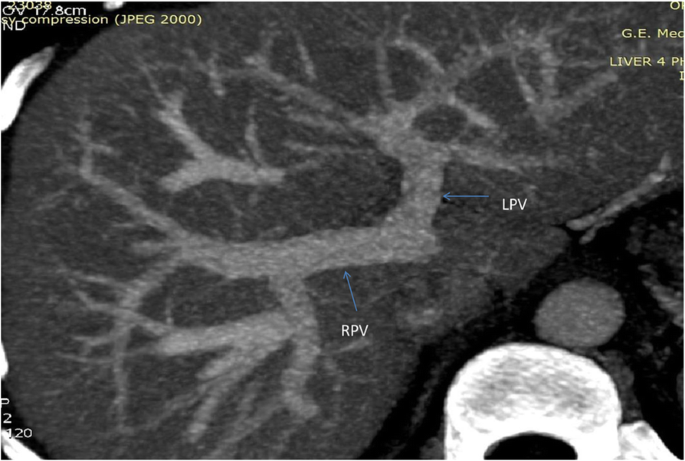

Portal Vein: Portal vein anatomy was Nakamura Type A (Fig. 2). The length of right portal vein was 11 mm. The significant crossover of the portal drainage was absent.

-